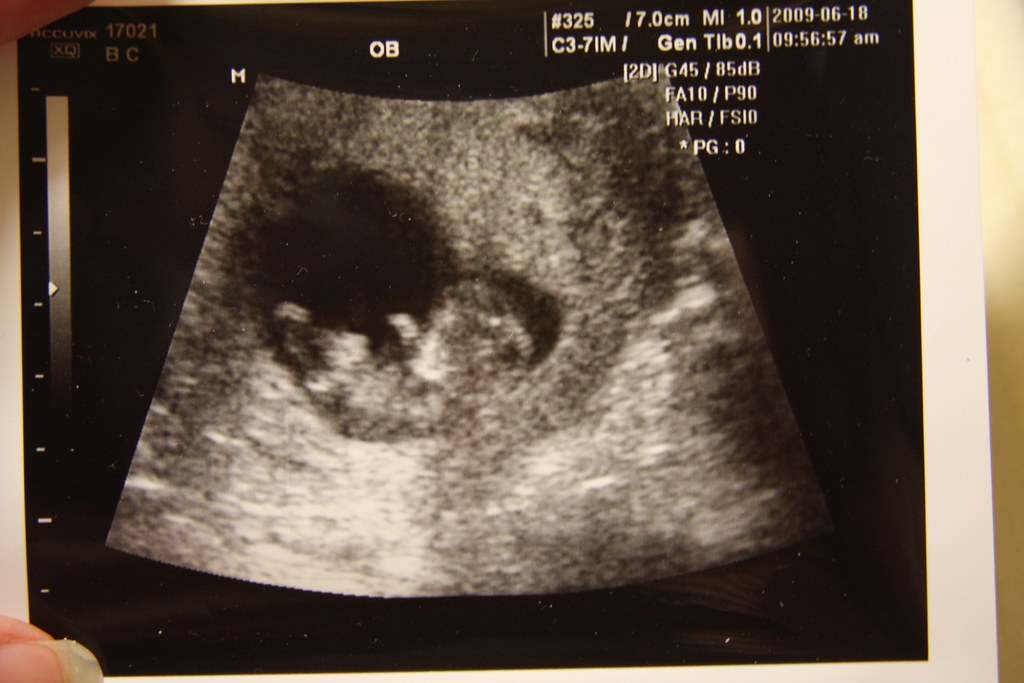

Photo credit: Flickr